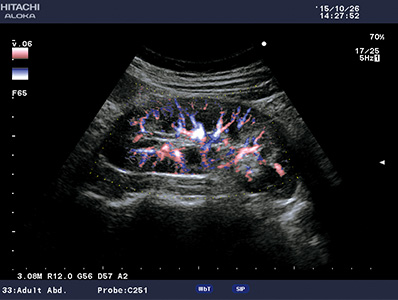

eFLOW

Provides clearer delineation between tissue and blood flow compared to conventional Color Doppler. Even low velocity flow can be imaged with high sensitivity.

Dual CF

Real-time B- and Color Flow modes can be displayed side-by-side, offering an easier anatomical interpretation of blood flow.